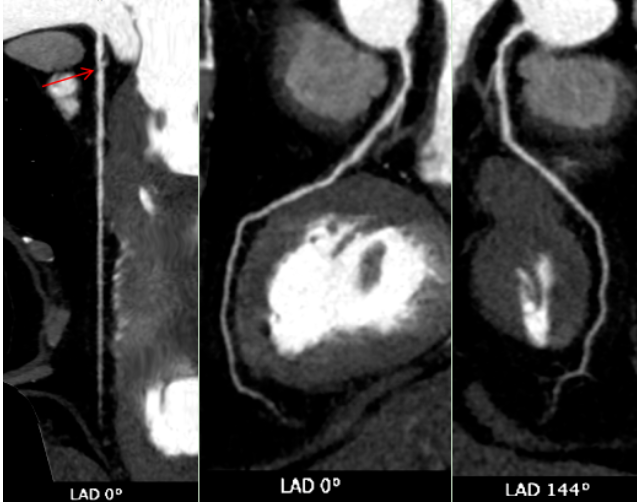

CT表现:冠状动脉粥样硬化,左冠状动脉前降支近端中度狭窄,左冠状动脉前降支心肌桥形成。

正常情况下,血管走在心脏表面,收缩舒张自由;而当血管被心肌“桥”覆盖时,心脏每次收缩挤压,都可能短暂压迫这段血管,影响远端的血液供应。狭窄加上心肌桥的叠加效应,很好地解释了他为何出现胸闷、胸痛(心绞痛)和心律不齐的症状——心肌正在发出“缺血”的求救信号。

冠状动脉CTA已成为筛查和诊断冠状动脉疾病的无创性“金标准”之一。它通过静脉注射对比剂,利用CT快速多层扫描和三维重建技术,直观展示冠状动脉的走行、管腔狭窄程度、斑块性质(如钙化斑块或软斑块)以及血管壁的情况。对于像张老先生这样的病例,CTA不仅能精准测量狭窄百分比,还能识别心肌桥这一解剖变异,评估其与狭窄的相互影响,为临床制定治疗方案(是药物保守治疗,还是需要介入支架或外科搭桥)提供了至关重要的参考。报告中提到的宽体探测器技术,代表了当前CT发展的前沿方向,特别适用于心率快、心律不齐、不能配合屏气或身体虚弱的患者,极大地拓宽了心脏CT检查的适用人群和诊断成功率。